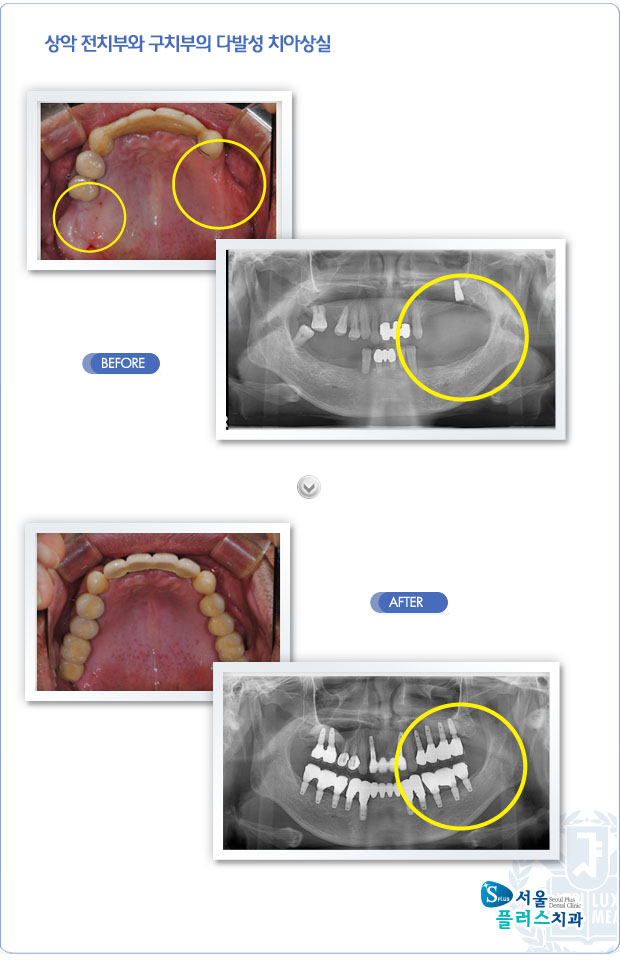

[임플란트] 상악 전치부와 구치부의 다발성 치아상실